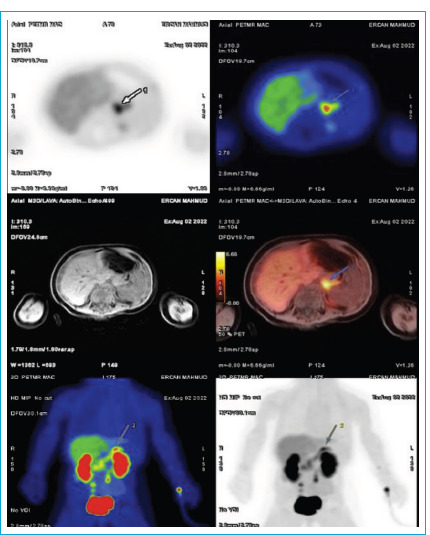

Congenital hyperinsulinism (HI) is the leading cause of persistent hypoglycemia in infants and children. Focal pancreatic lesions account for 30-40% of cases with congenital HI. With early diagnosis, these patients can be treated by resection of the lesion, making long-term medical care unnecessary. In this case, a 5-day-old newborn boy presented with convulsion due to severe and persistent hypoglycemia at his hospitalization in neonatal intensive care unit. Laboratory studies revealed very low levels of ketone bodies with inappropriately normal insulin levels during hypoglycemia. The patient was unresponsive to diazoxide treatment. The molecular genetic analysis revealed a heterozygous pathogenic variant in the ABCC8 gene. 18F-DOPA-PET/CT scan showed increased uptake of 18F-DOPA consistent with focal lesion at the tail of the pancreas. A focal pancreatectomy operation was performed when he was three months old. Histopathological evaluation confirmed focal endocrine cell hyperplasia. Hypoglycemia did not recur after the operation. CHI patients with ABCC8 / KCNJ11 mutation are not easy to manage with pharmacotheraphy. In the case of an identifiable focal lesion associated with CHI, surgery is the most preferred option. In focal CHI, as in our case, the lesion may not be visually evident and requires a surgeon experienced in CHI.